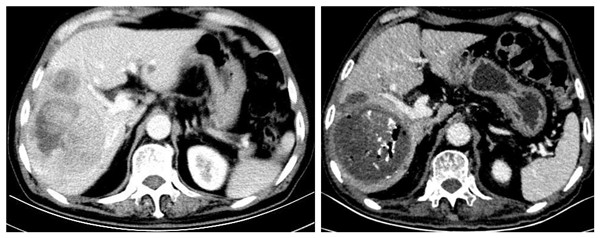

患者为69岁的老年男性,因“消瘦和腹部不适”于我院消化内科就诊,影像学提示“原发性肝癌”,肿瘤位于右半肝, CNLC分期 Ⅲa期。经我院肝癌多学科诊疗团队(MDT)评估,考虑患者肿瘤体积大且肝功能不佳,决定先行一期经肝动脉化疗栓塞(TACE)联合索拉非尼转化治疗,待肿瘤体积缩小后再进行二期手术治疗。一期TACE联合索拉非尼治疗由消化内科戴社教教授和袁佳主治医师完成。治疗后肿瘤体积明显缩小,坏死面积80%以上,达到影像学部分缓解,为行二期手术治疗转入普通外科陆宏伟教授组。

TACE术前 TACE术后